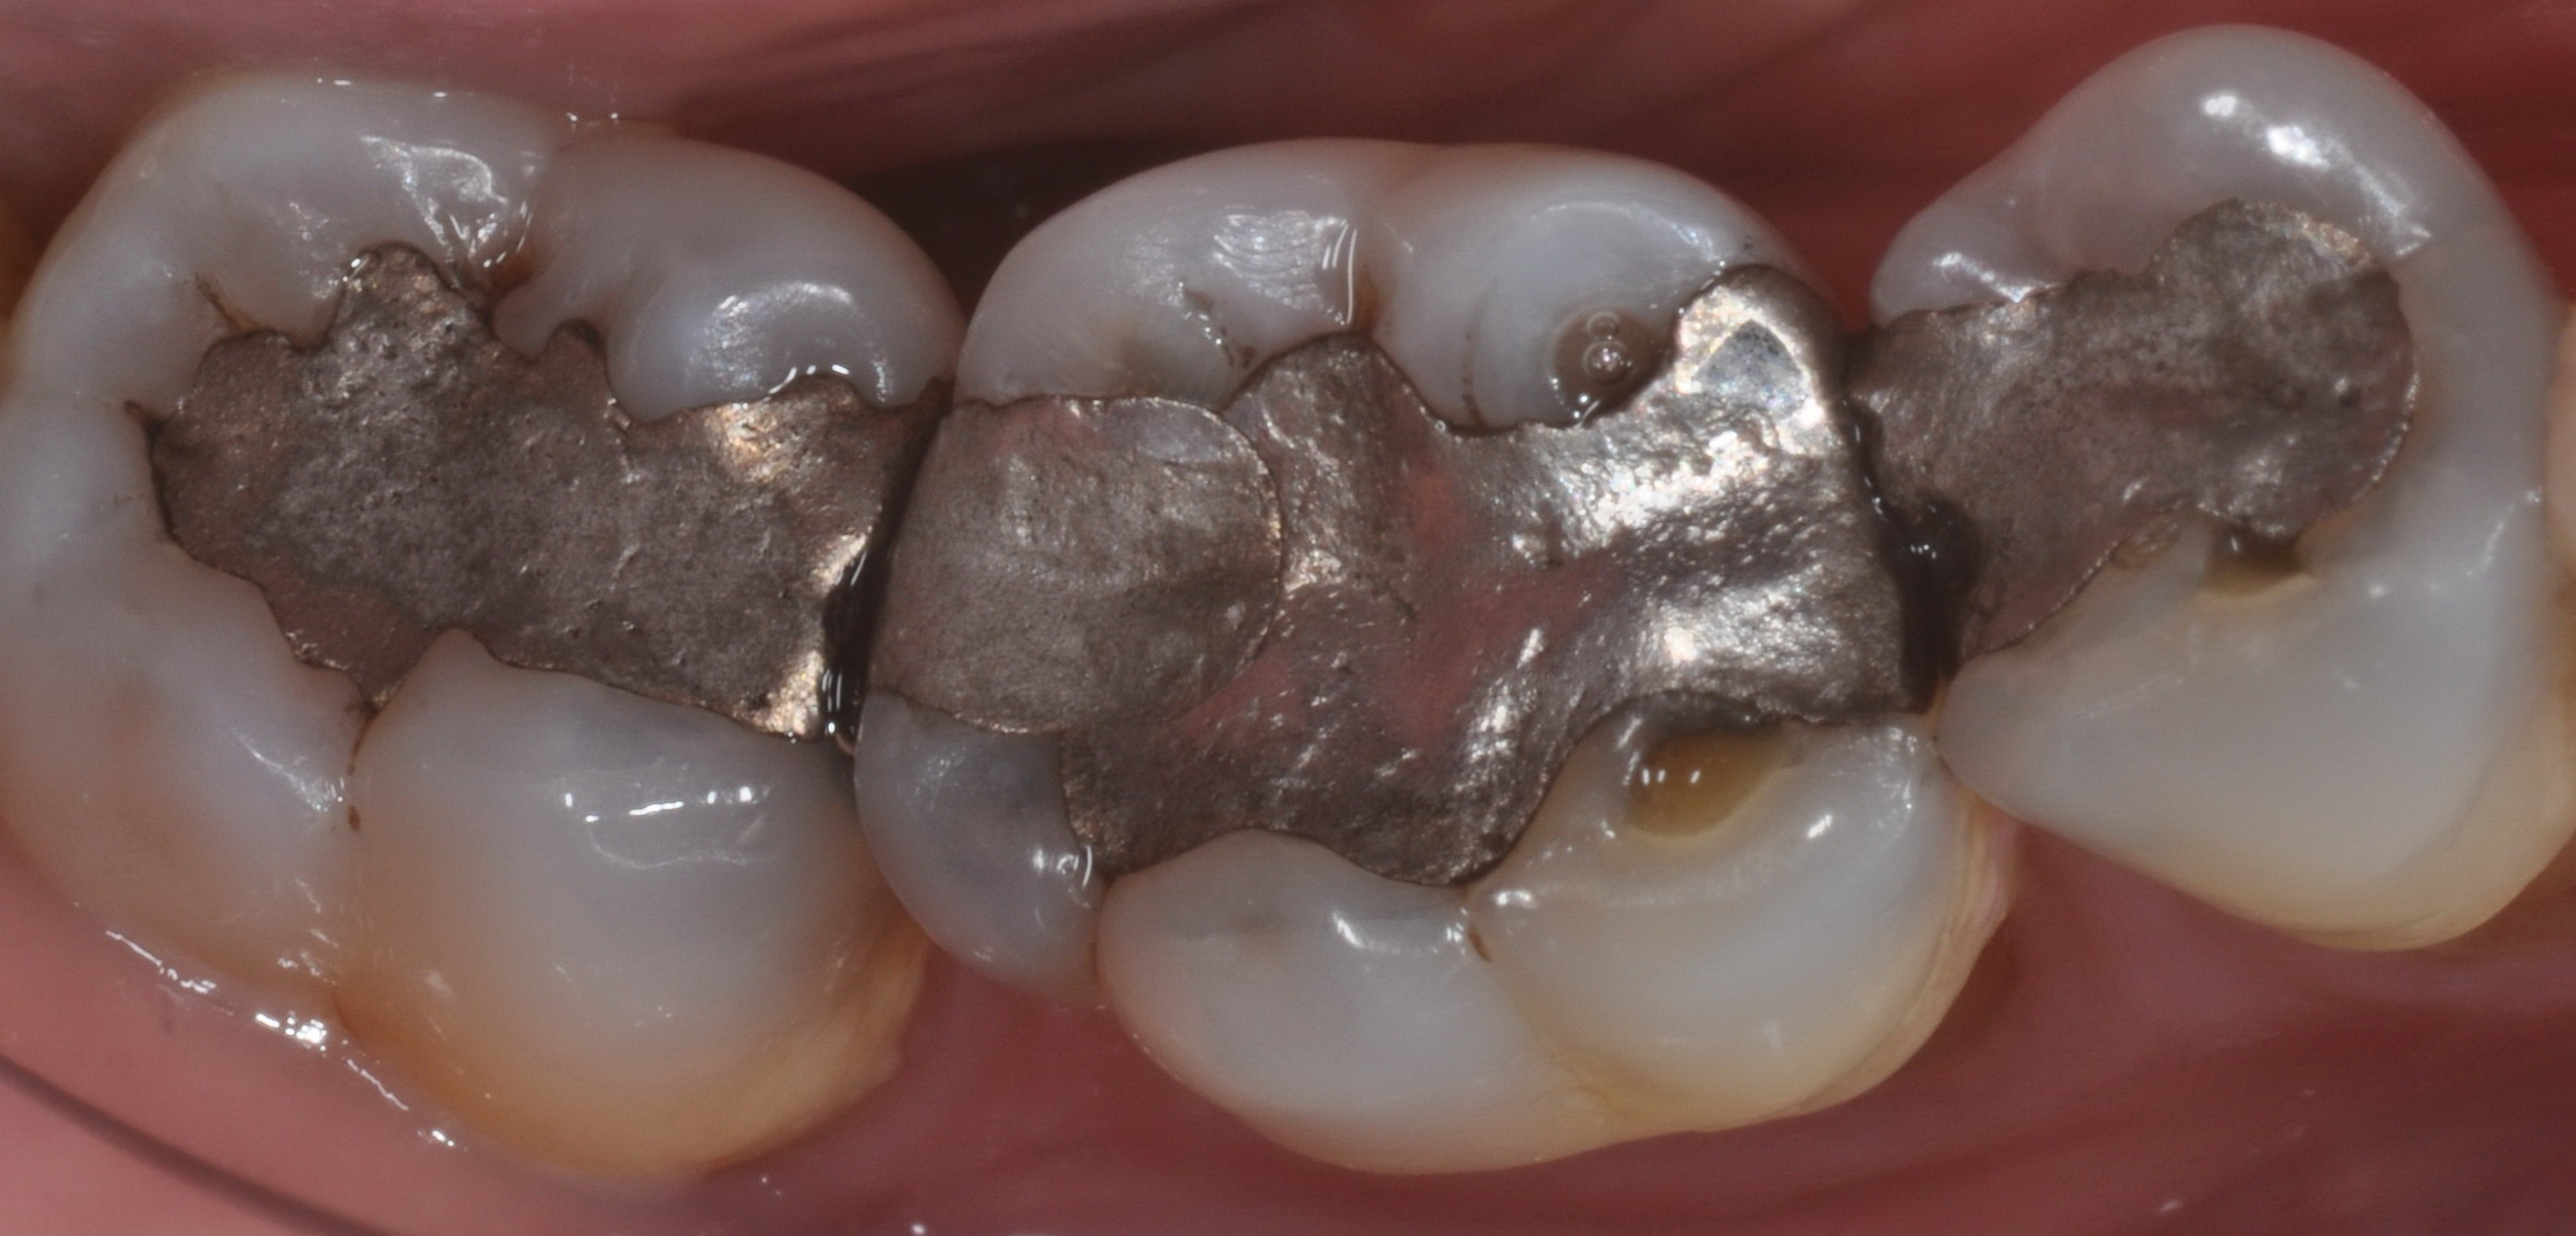

Prima

Presenza di otturazioni in amalgama.